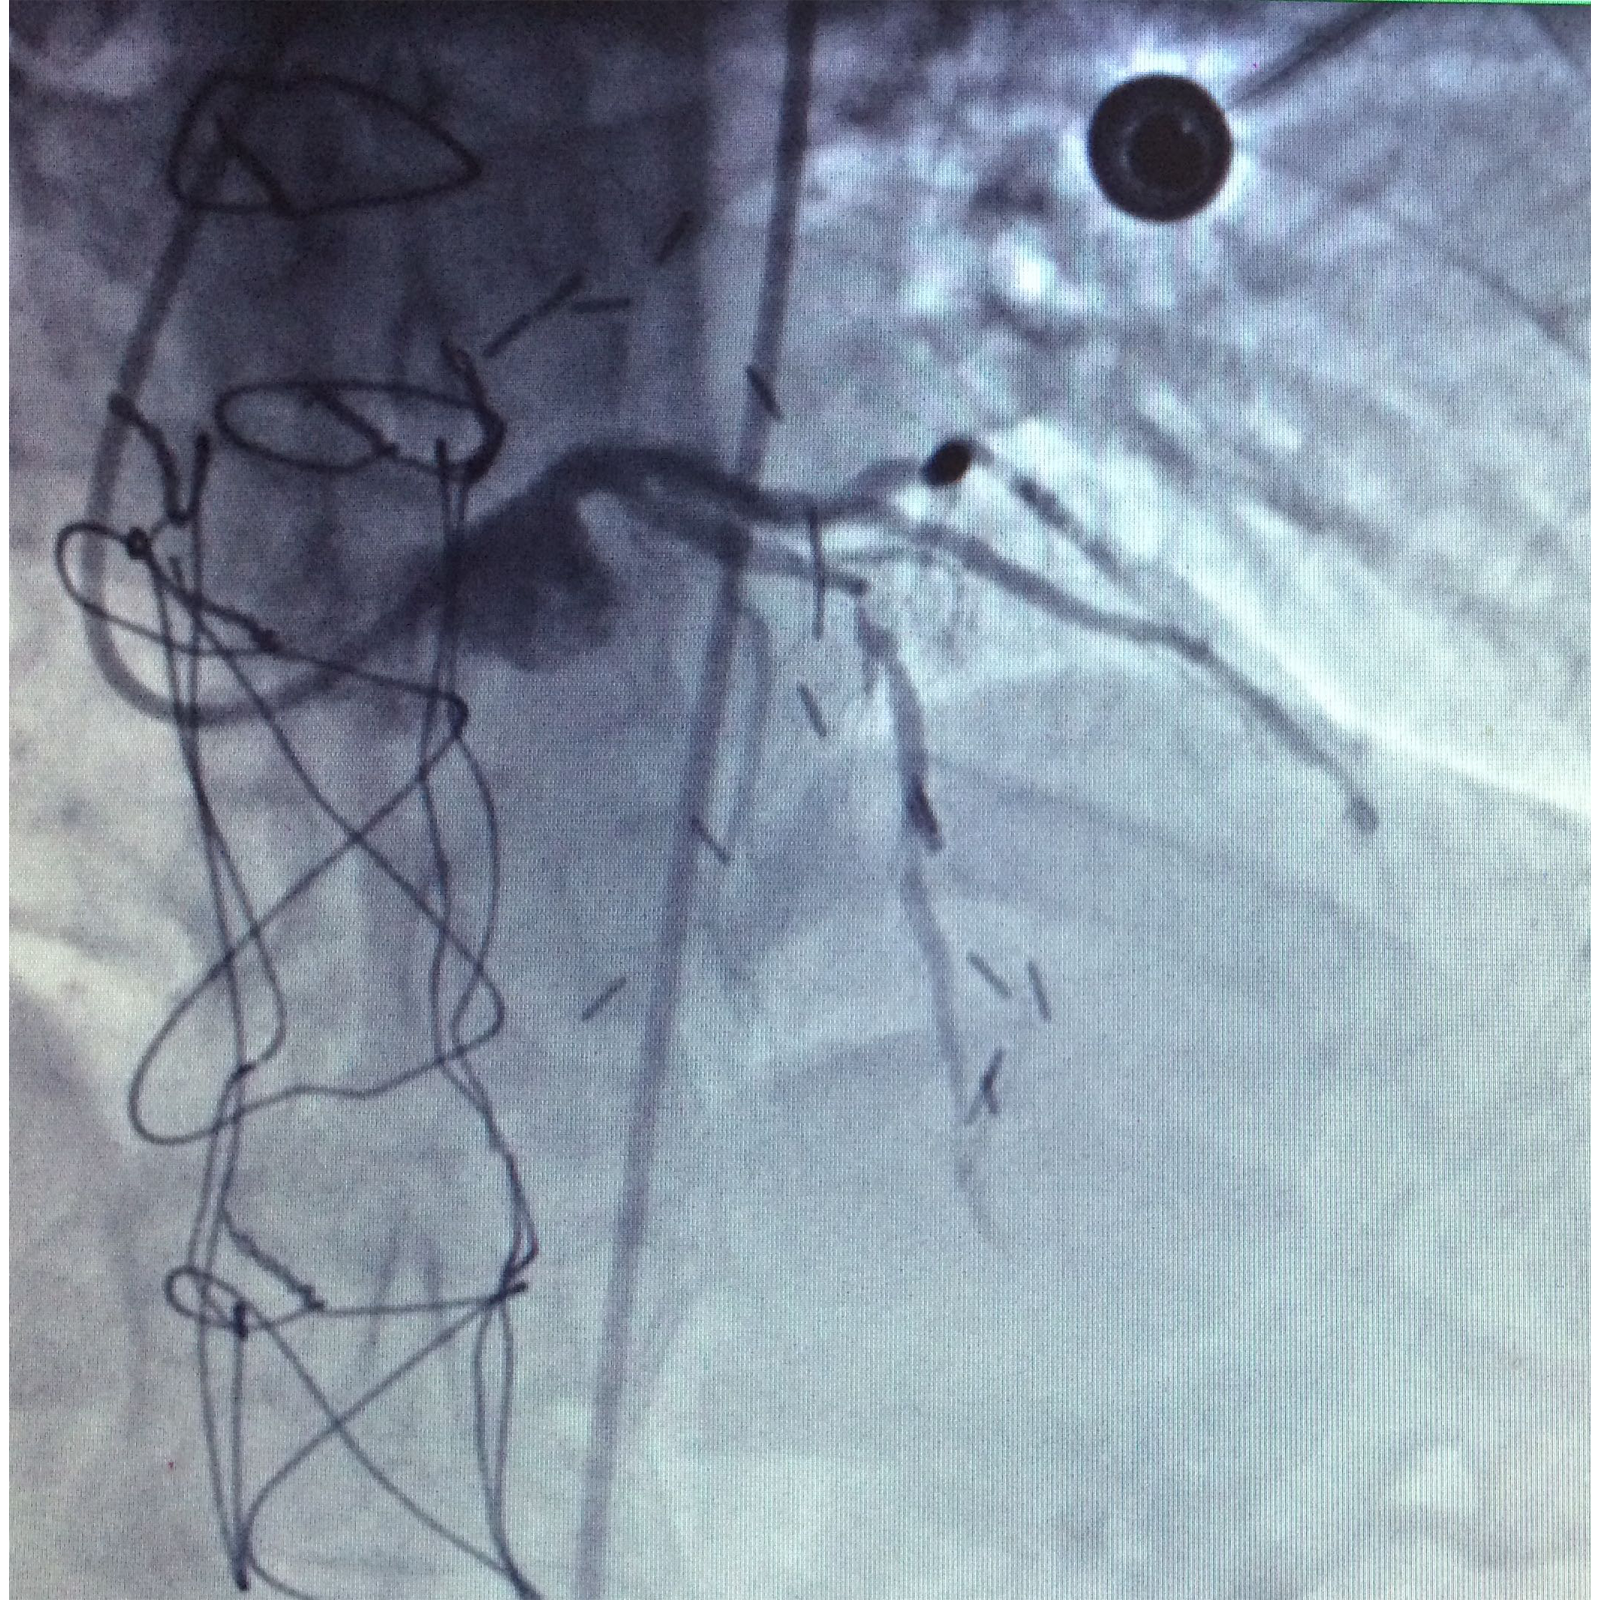

Figure 3 Through a conventional right femoral approach, the left coronary ostium was canalized using a 4.0 6Fr Launcher guiding catheter (Medtronic). Subsequently, a floppy microguide at the level of the anterior left descending artery was used to cross the lesion. Balloon dilation was performed to open the vessel starting with a 1.5x18mm Sprinter balloon (Medtronic) followed by a 2.0x22mm to finally deploy a 2.5x18mm Endeavor stent at 18atm for 10 seconds at the level of left anterior descending artery obtaining a satisfactory angiographic result.

Procedure

Through a conventional right femoral approach, the left coronary ostium was canalized using a 4.0 6Fr Launcher guiding catheter (Medtronic). Subsequently, a floppy micro guide at the level of the anterior left descending artery was used to cross the lesion. Balloon dilation was performed to open the vessel starting with a 1.5x18mm Sprinter balloon (Medtronic) followed by a 2.0x22mm to finally deploy a 2.5x18mm Endeavorstent at 18 atm for 10seconds at the level of left anterior descending artery obtaining a satisfactory angiographic result (Figure 3-6).

Figure 4 Through a conventional right femoral approach, the left coronary ostium was canalized using a 4.0 6Fr Launcher guiding catheter (Medtronic). Subsequently, a floppy microguide at the level of the anterior left descending artery was used to cross the lesion. Balloon dilation was performed to open the vessel starting with a 1.5x18mm Sprinter balloon (Medtronic) followed by a 2.0x22mm to finally deploy a 2.5x18mm Endeavor stent at 18atm for 10 seconds at the level of left anterior descending artery obtaining a satisfactory angiographic result.